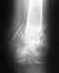

здравствуйте!в ЛПУ потеряли амбулаторную карту ,а мне надо срочно точный клинический диагноз, в 1988г.была резанная травма 4\5ахиллова сухожилия в области пятки левой ноги. никто из хирургов не ставит, не знаю по какой причине просто описывают жалобы. онемение пятки большого пальца на левой ноге онемение с внешней стороны большой мышцы.пальцы не двигаются. опухание большой берцовой мышцы постоянные боли. с чего или с кого начать чтобы получить диагноз. извините, если можно -заочно как будет выглядеть этот диагноз. спасибо

Спасибо,Александр что ответили!резаная рана 4\5 ахиллова сухожилия в области пятки.это запись на справке травмпункта (всё ,что осталось все карты в ЛПУ утеряли).поход к хирургам,неврологам ничего не дают-пишут жалобы на постоянные боли,и т.п.а дигноз не ставят.а если сказать что пытаюсь получить "посыльный лист" на мсэ(это заболевание как вторичное)я пытался один разок мне в новой карте написал:"требуется операция пупочная грыжа"я к нему с ногой -а они...грыжа , лечиться уже поздно травме 20 лет.какой вот может быть диагноз? хотя бы заочно.был один ответ из сети-нейропатия.?!